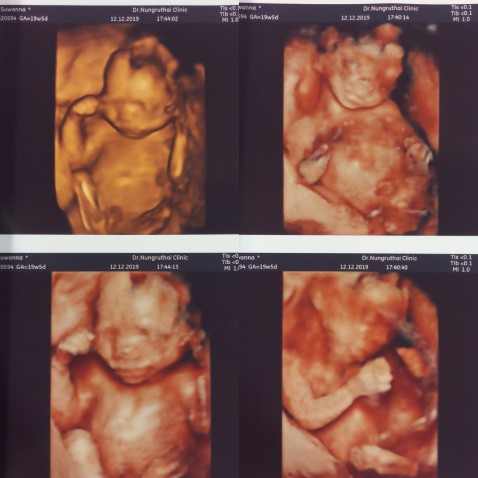

โชว์ผลซาวด์กันค่ะ

คุณลุงหมอบอกมีกลีบ?ใครมีกลีบ ใครมีแท่ง ลงมาอวดกันจร้า

กองก้น โชว์ใข่ชัดมากกค้ะ 14 Week5Day😁💕

บ้านนี้มีกลีบค่ะ ชัดแจ๋ว😊😊

หมอบอกว่าหนูไม่มีจู๋คะ 😁😁😁

บ้านนี้มาเป็นแท่งเลยค่ะ 😄😊

ทั้งพวงทั้งแท่งเลยคร้าบ 😊😁

คุณหมอบอกผู้ชาย100%คร้าบบบ😂😂

ท้องสองกลีบอีกแล้วววค่ะ😂😂

จู๋ชัดมากค่ะ..5เดือนแล้ว